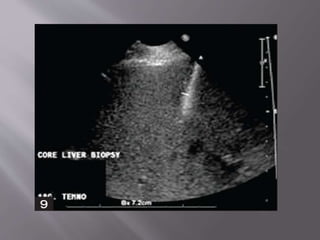

 Liver biopsies areperformed for both focal and nonfocal lesions.  The primary indication for parenchymal liver biopsy is for the diagnosis of hepatic disease.

• 54.

  When imaging guidanceis employed, it can take one of two forms: US-guided "marking" in which a mark is made upon the skin during US examination for a biopsy to be performed later without imaging guidance or real-time US guidance.

• 55.

 The patient ispositioned supine, with the hands comfortably resting behind the head  A preliminary US scan is performed to identify the target and mark the skin.

• 56.

 The preliminary scanalso ensures that no major vessels, dilated biliary channels or gall bladder are in the path of the biopsy needle.

• 57.

 Before the procedureis started, breathing instructions are practiced with the patient.  performed with the breath held in expiration.  This minimize risk of injury to the pleura or lung.

• 58.

 The skin siteis prepped and draped to ensure asepsis The local area is anesthetized with a local anesthetic.  The cutting needle is then fired with US documentation of the site.